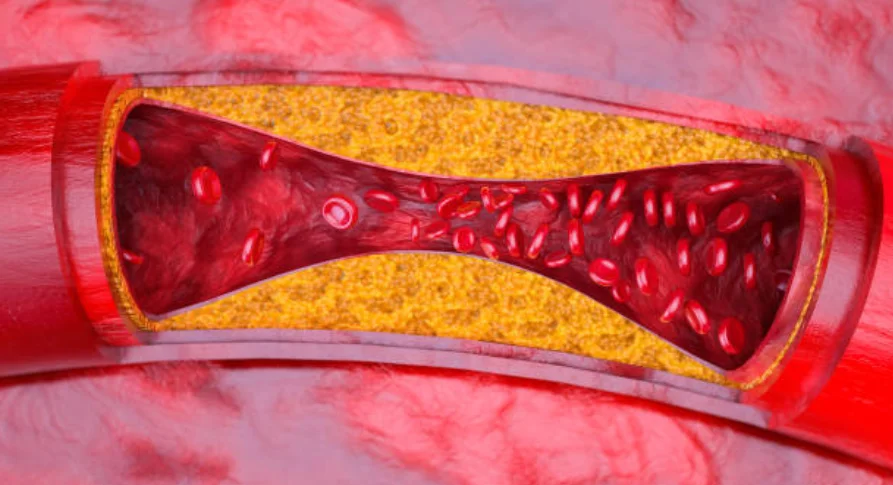

要は動脈硬化みたいな感じで根管が塞がってきているイメージですね。